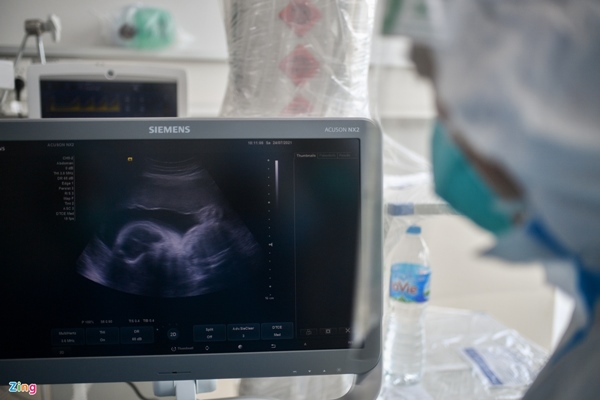

Đều đặn mỗi buổi sáng, anh đến khám, cho thuốc và siêu âm thai nhi. "Chúng tôi đặt mục tiêu phải đảm bảo sự an toàn cho cả 3 mẹ con", nam bác sĩ chia sẻ.

Bác sĩ Trần Thanh Linh và bác sĩ Trần Hữu Chinh siêu âm và theo dõi tình trạng thai nhi của chị T.

Điều trị Covid-19 cho những bệnh nhân mang thai rất phức tạp. Một số loại thuốc có nguy cơ ảnh hưởng đến thai nhi như kháng sinh, thuốc giãn cơ. Vì vậy, bác sĩ Chinh cùng đội ngũ đang cố gắng ngừng thuốc càng sớm càng tốt.

"Ngày nào thấy được sinh hiệu, tim thai tốt thì chúng tôi mừng ngày đó. Với tình trạng tiến triển như hiện tại của bệnh nhân, chúng tôi sẽ giảm dần máy thở và giảm ECMO, tập cho nữ bệnh nhân tự thở. Nếu thuận lợi, khoảng 4-5 ngày nữa sẽ cai máy thở", bác sĩ Chinh chia sẻ.